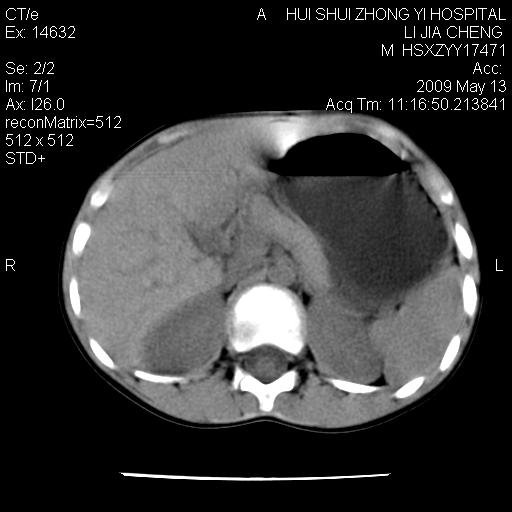

标题: PED1887:男性,6岁。反复脐周疼痛2年余。请各位老师看下腹 [打印本页]

标题: PED1887:男性,6岁。反复脐周疼痛2年余。请各位老师看下腹

该患者可自行好转,大小便未见异常,化验:便未见虫卵,血常规:wbc:8000;淋巴3600,中性45%

脂肪肉瘤可能性大,大血管边界不清,特别是腔静脉。不除外其他腹膜后肿瘤。

是不是有蛔虫哦,楼主图示块影前方肠管壁显著增厚,不除外慢性肠炎或肠壁占位,建议肠道准备后复查

来源于十二指肠水平部病变?建议行进一步检查。

肠管管壁均匀增厚,炎性可能

是小肠,壁稍厚可能是肠腔未很好充盈所致,腹部ct扫描未见明显异常。